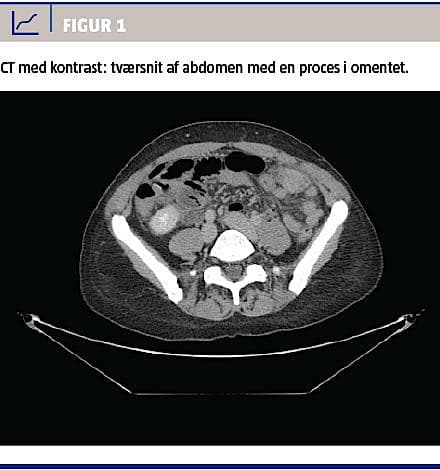

Ved en gynækologisk undersøgelse fandt man normale forhold med en spiral in situ. De vitale parametre var upåfaldende. En biokemisk undersøgelse viste normalt hæmoglobinniveau, basisk fosfatase og negativ S-humant choriongonadotropinniveau, men forhøjet C-reaktivt proteinniveau til 16 mg/l og alaninaminotransferaseniveau på 77 E/l. En CT af abdomen med i.v.-kontrast viste en atypisk inflammatorisk proces i venstre side af abdomen (Figur 1 og Figur 2), og der blev udført diagnostisk laparoskopi på mistanke om inflammeret Meckels divertikel. Ved laparoskopien fandt man i omentum majus en solid tumor, som var adhærent til forreste bugvæg. Efter at man havde sikret sig, at der i øvrigt var normale forhold intraabdominalt, blev tumoren laparoskopisk fjernet en bloc. Makroskopisk vurderet var tumoren 45 × 40 × 20 mm. På snitfladen var den fast heterogen med fedtvævslignende områder og nekroselignende forandringer centralt. Ved mikroskopi af omentet påvistes Actinomyces med karakteristiske sulphur granules bestående af bakterier og inflammatoriske celler (Figur 3). Dyrkning af ascitesvæske og podning fra IUD og cervix viste ingen vækst af Actinomyces. Efter konstatering af Actinomyces fik patienten fjernet spiralen og blev sat i i.v.-behandling med penicillin 5 mio. IE × 4 dagligt i 13 dage, efterfulgt af otte dages behandling med clindamycin 900 mg. Derefter blev patienten behandlet med amoxicillin 750 mg × 3 dagligt.

Abdominal aktinomykose kan give diagnostiske vanskeligheder, da symptomerne er ukarakteristiske og ofte opstår længe efter den udløsende årsag. Billeddiagnostik og laboratorieprøver er ligeledes uspecifikke, hvorfor symptomerne ofte tolkes som hidrørende fra en malign tumor [3]. Ved abdominal aktinomykose har præoperativ diagnostik uden biopsi en succesrate på op til 10% [3]. CT fører ofte til kirurgisk indgreb pga. tumormistanke.